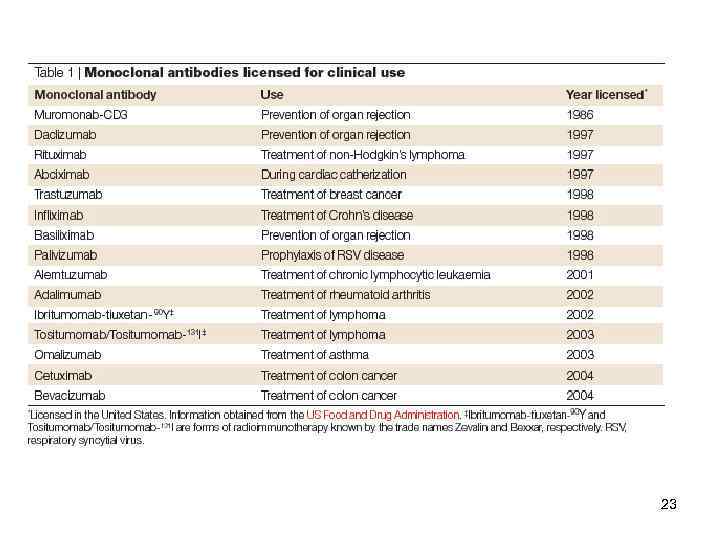

Функции АТ Passive antibody therapy for infectious diseases Arturo Casadevall, Ekaterina Dadachova & Liise-anne Pirofski Nature Reviews Microbiology 2, 695 -703 (September 2004) 20

Функции АТ Passive antibody therapy for infectious diseases Arturo Casadevall, Ekaterina Dadachova & Liise-anne Pirofski Nature Reviews Microbiology 2, 695 -703 (September 2004) 20